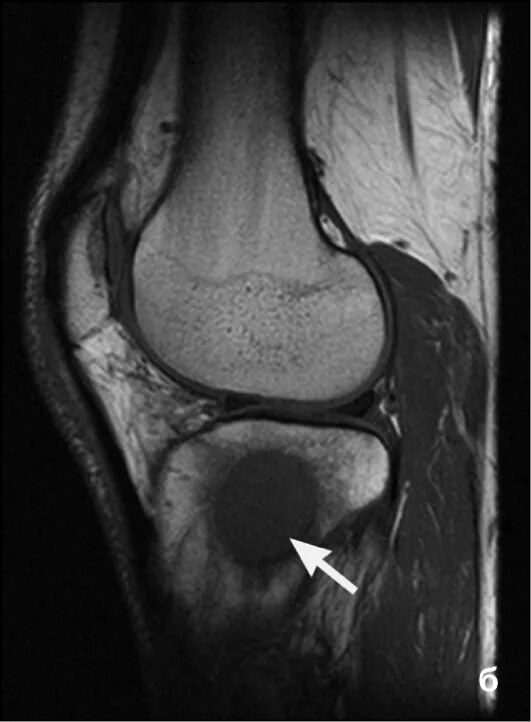

Метастазы костных тканей